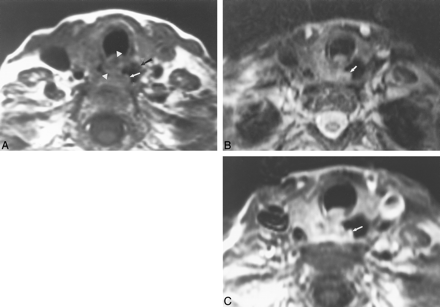

This 66-year-old man had direct EI by laryngeal carcinoma, resulting in a tracheo-esophageal fistula.

A, Axial T1-weighted image (600/17) shows a mass that surrounds the esophagus (arrows) by approximately 270o. The fat plane between the mass and the esophagus is obliterated. The esophageal lumen contains air.

B, Axial T2-weighted image (4000/80) shows focal increased signal (arrow) in the esophageal wall adjacent to the mass.